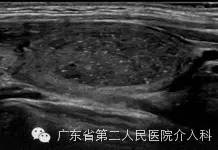

上图门诊超声提示:甲状腺右叶下极结节,血流丰富,代谢旺盛。